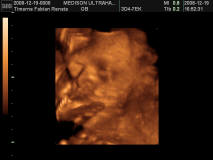

keresztbe tett lábak és a zacsi